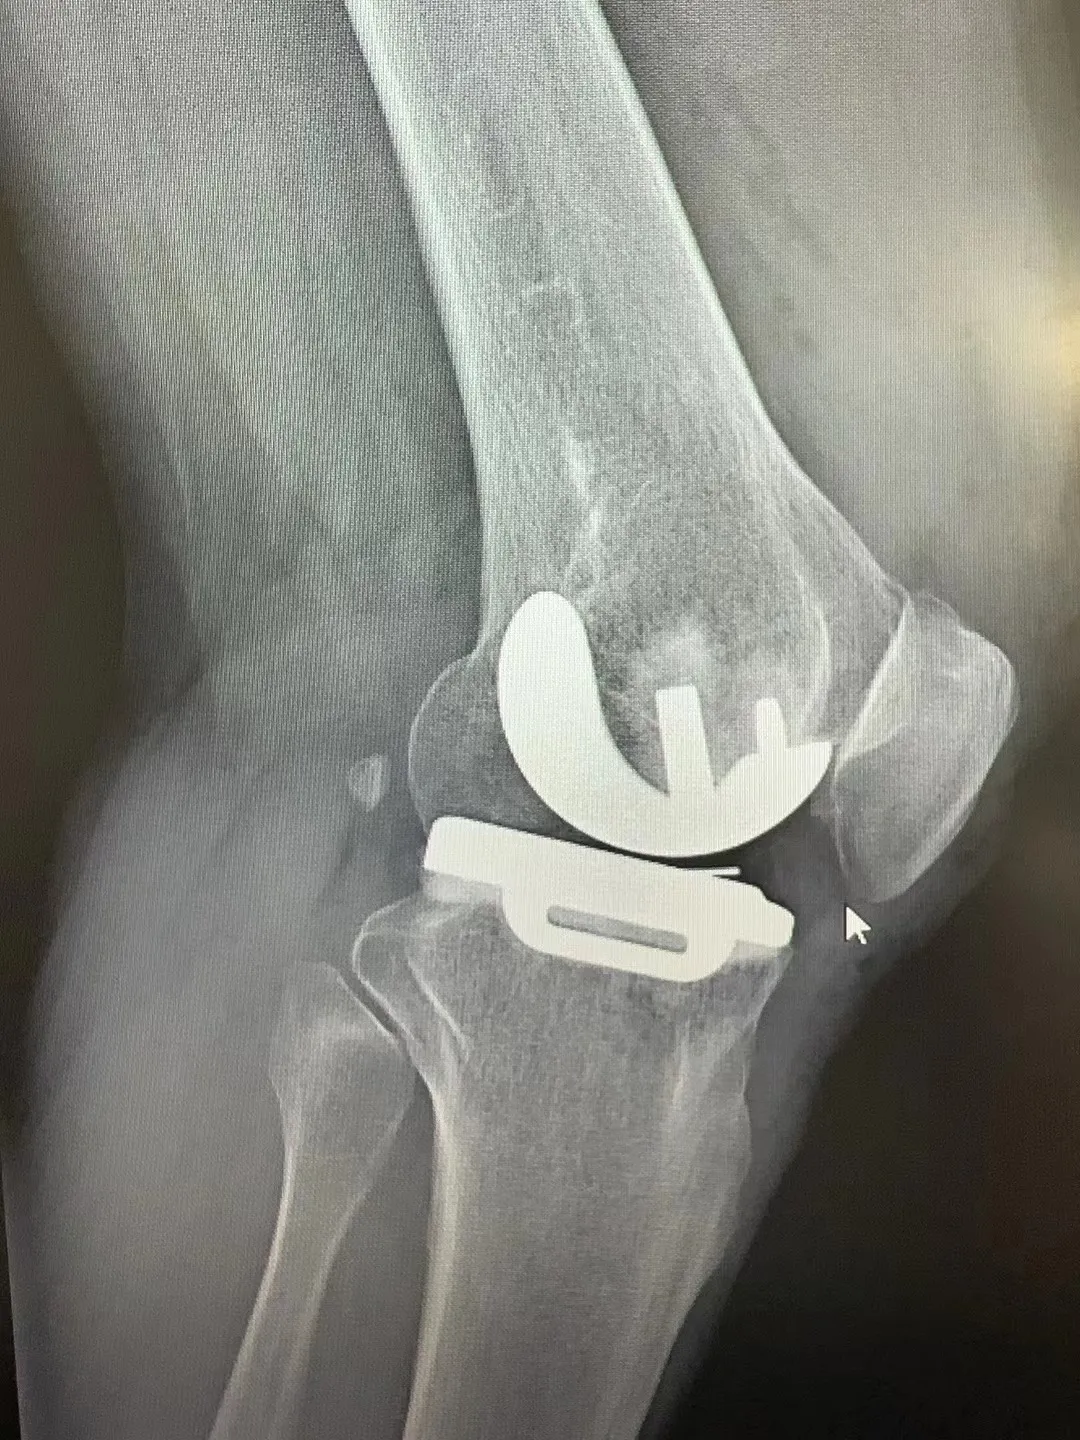

患者术前膝关节情况

术后患者膝关节情况